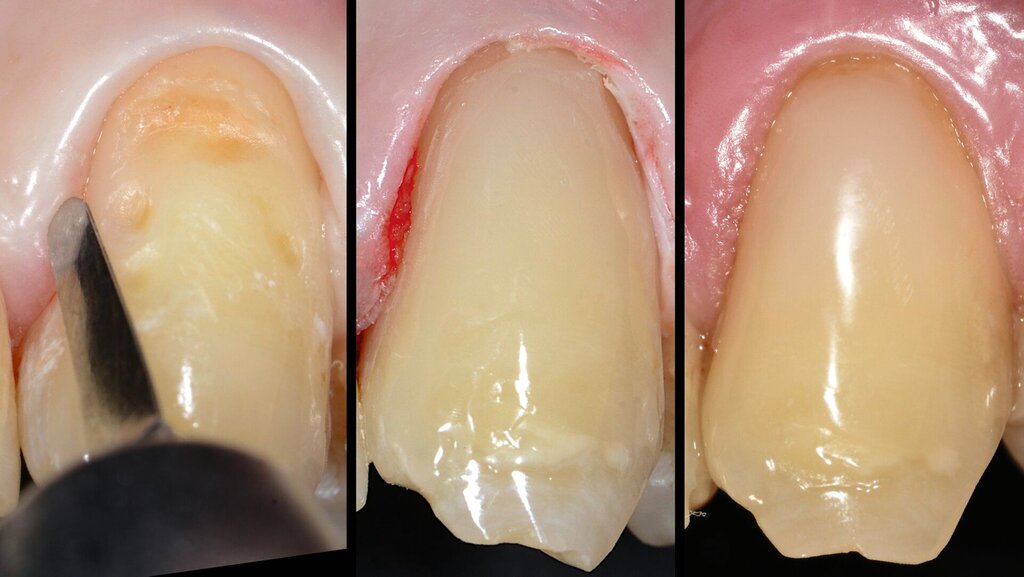

Nach diesem Schema wurden weitere Portionen des fließfähigen Materials appliziert, bis eine Art „Wanne“ im zervikalen Bereich ausgeformt war. Nach Aufbringen der letzten Portion wurde eine Lichtpolymerisation von 20 Sekunden vorgenommen. Im Anschluss daran konnte hochviskoses Kompositmaterial mit einem kleinen Spatel in die Kavität appliziert und abschließend für 20 Sekunden lichtpolymerisiert werden (Abbildung 2e).

Die Ausarbeitung und Politur der Restauration erfolgten mit oszillierenden, diamantbelegten Feilen, Steinchen und Silikonpolierern (Abbildung 2f). Nach einem halben Jahr sowie drei Jahre nach Applikation erwies sich die Restauration weiterhin als funktionstüchtig (Abbildungen 2g und 2h).